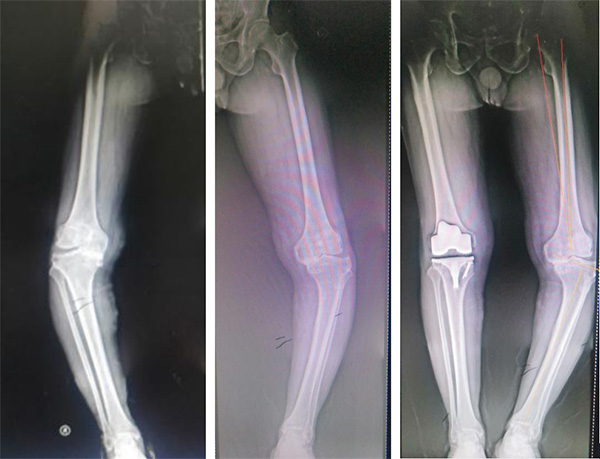

图3 双膝关节骨关节炎,内翻畸形严重,行右侧全膝关节置换术